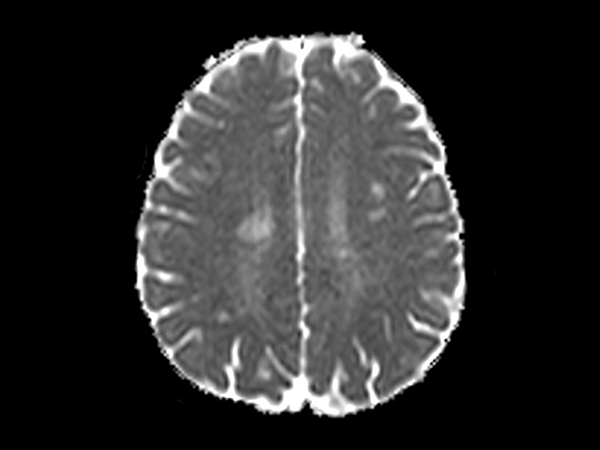

Brain - White matter lesions

Fast and high quality brain imaging for a patient with white matter lesions. AI based SmartSpeed is utlized to shorten scan time without compromise in image quality. Advanced 3D TSE imaging technique are used to acquire high resolution data in multiple directions in only one single scan.

Axial DWI b1000